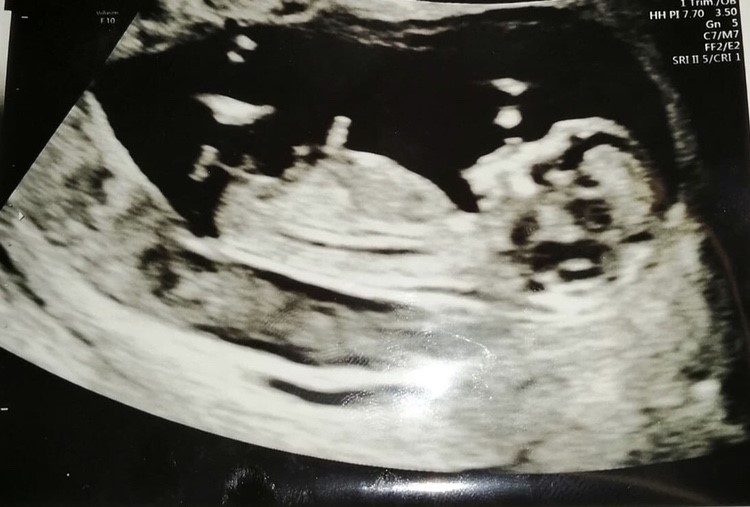

Jeg er 12+6 i dag og blev kaldt ind til Nakkefold 12+1.

Det hele forløb så smukt, hoppede, svømmede og spjættede rundt blev kaldt en rigtig sprællerbasse, normalt fostervand jamen det var tip top.

mine tal lød på 1: 20.700 skulle jeg mene der omkring så meget meget lav risiko fik jeg atvide, og som det så ud nu var der slet ikke en finger at sætte på baby og hun sagde at vi med sikkerhed kan tage hjem og nyde graviditeten til fulde nu